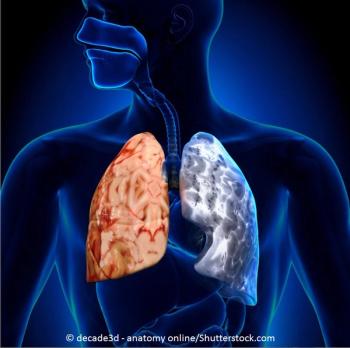

Beth is age 52, smokes 2 packs of cigarettes a day, gets breathless in cold weather, and has had "bronchitis" twice this year. What's your diagnosis?